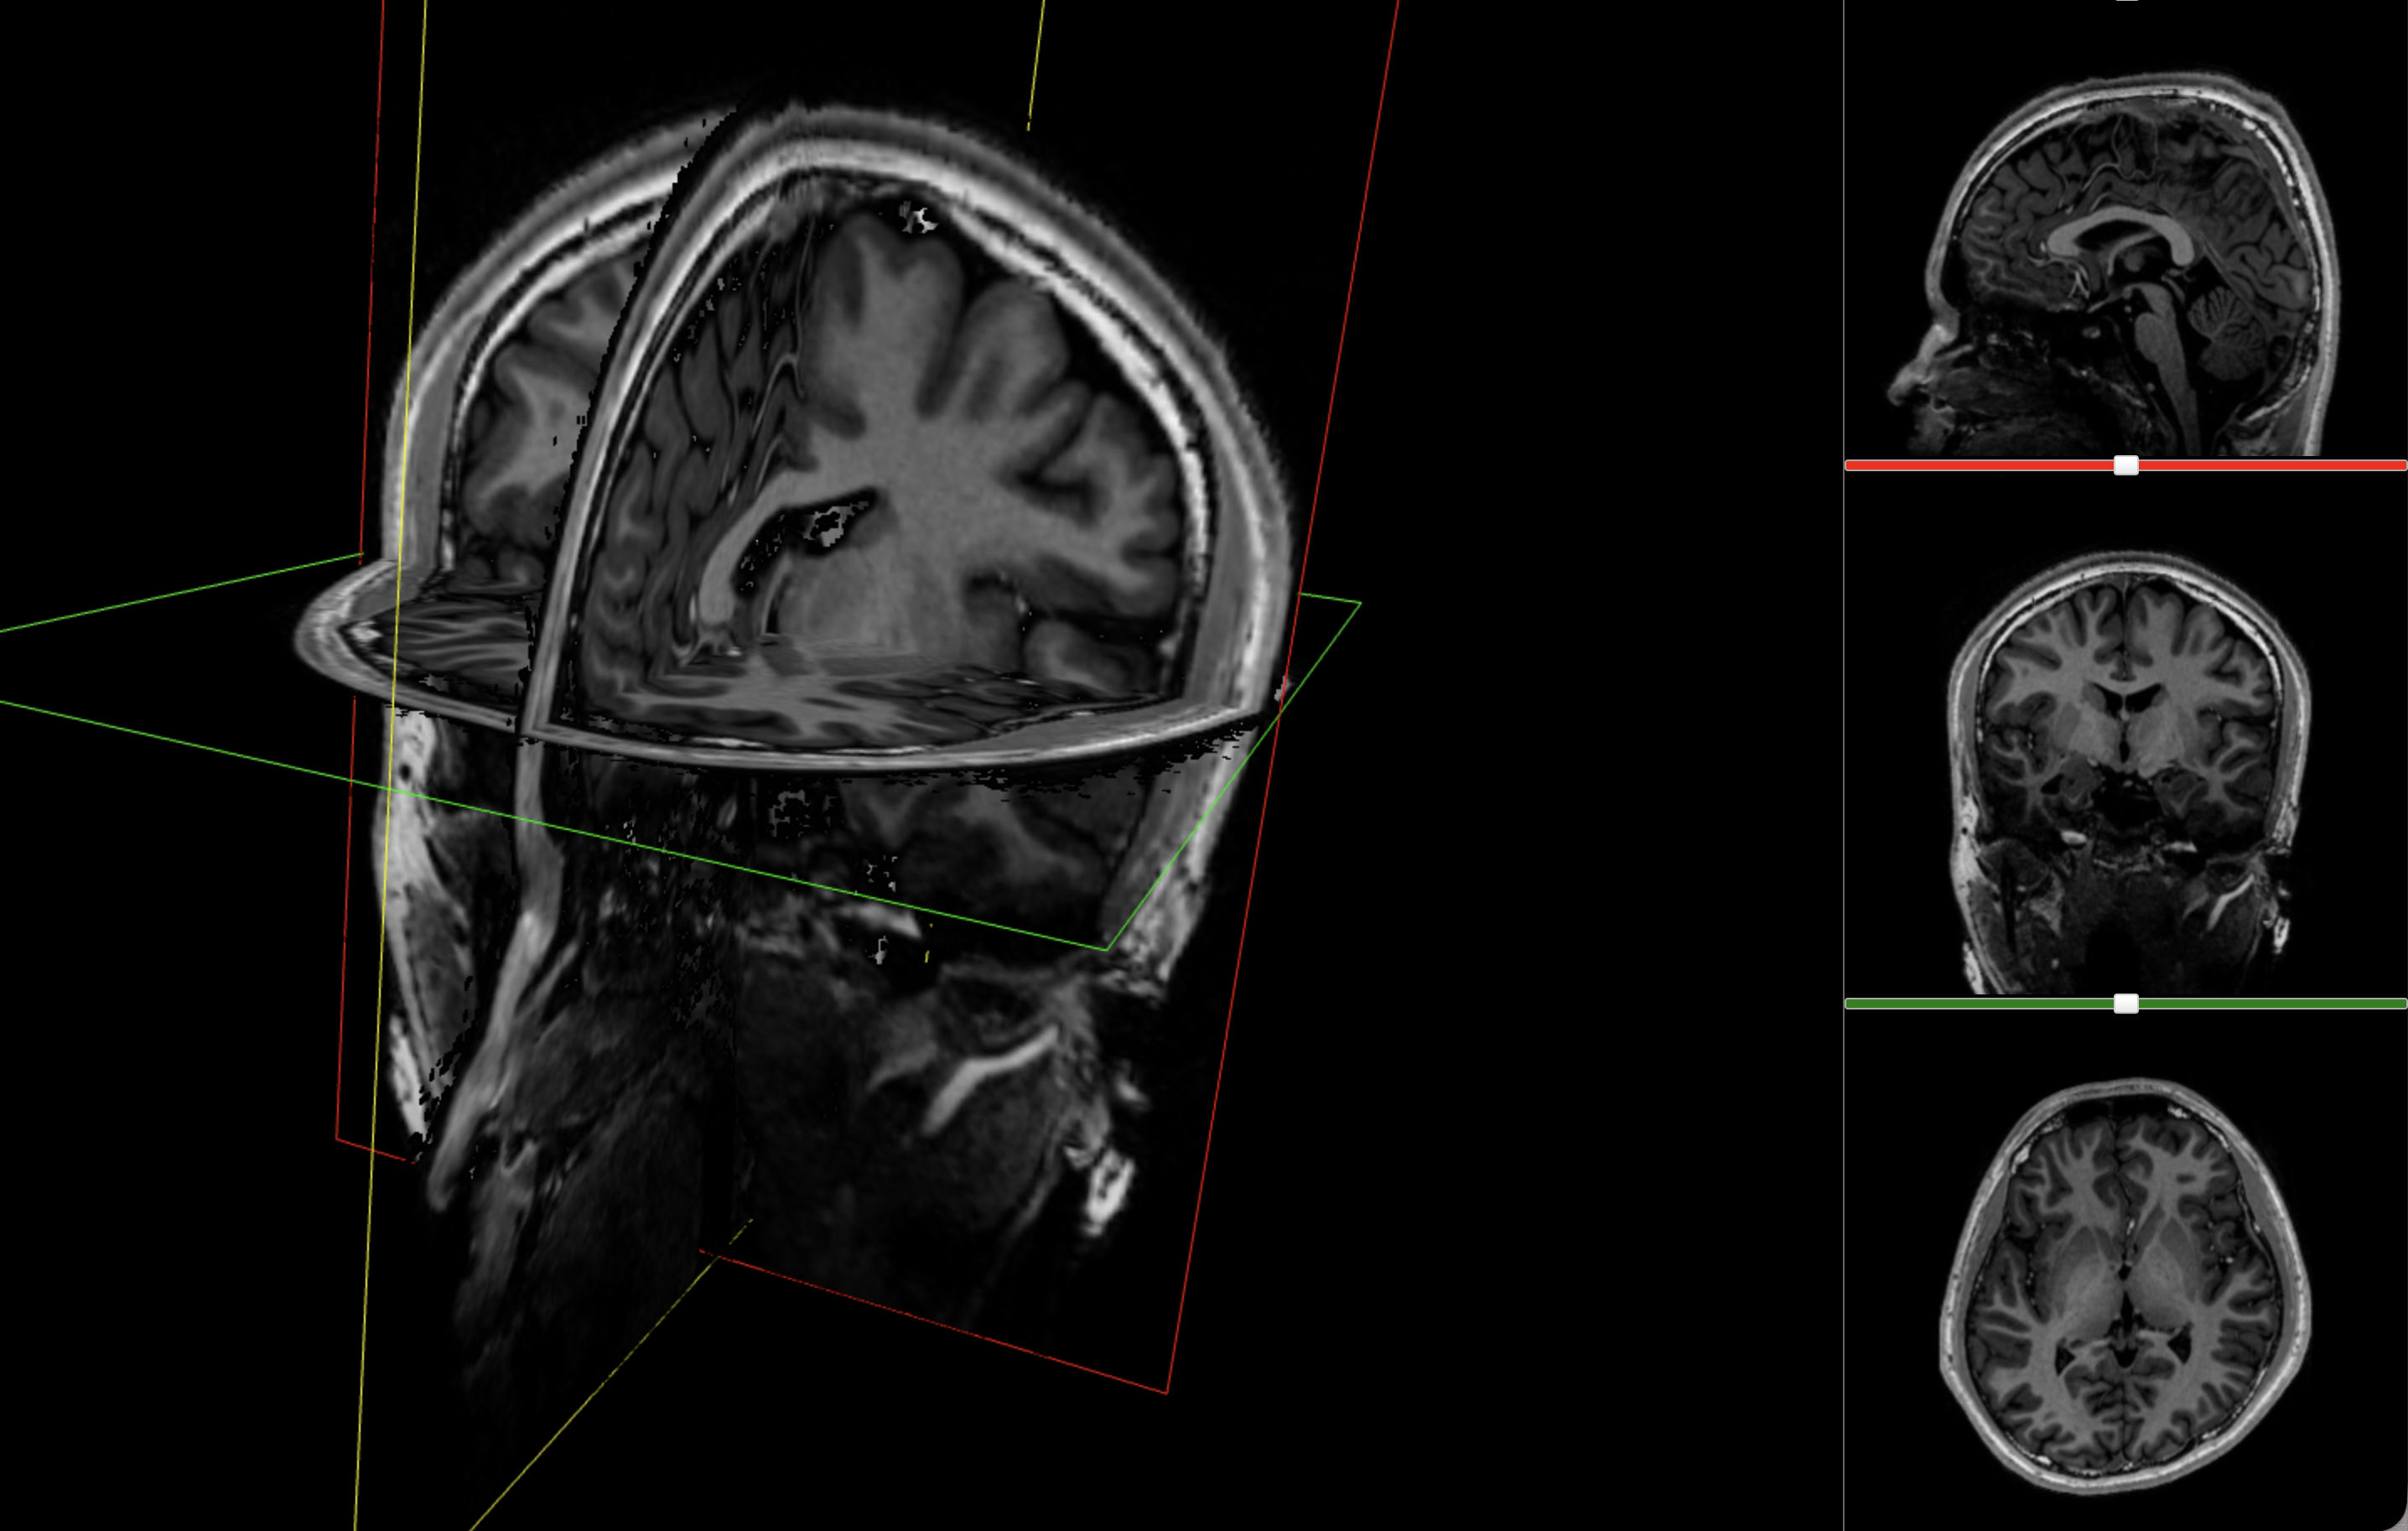

After the four-hour analysis, FreeSurfer had already given me what I needed to inspect the scan: a segmented volume that could be overlaid directly on the anatomical MRI. Visualising that (using a tool like ITK-SNAP), I got something a bit more interpretable than the original slices:

These are three orthogonal slices of my brain, with borders drawn around FreeSurfer’s own segmentations.

What I liked about having this data was that it changed how I interacted with the scan. Instead of staring at individual slices and guessing at the composition, I could start isolating specific parts of the brain.

The visualisations above show how little differentiation some brain regions have from their surroundings - I knew roughly where the thalamus was in the brain, but would never have been able to point it out on the MRI. At this stage, FreeSurfer plus some code had given me a perspective that would have been impossible for me to achieve myself.